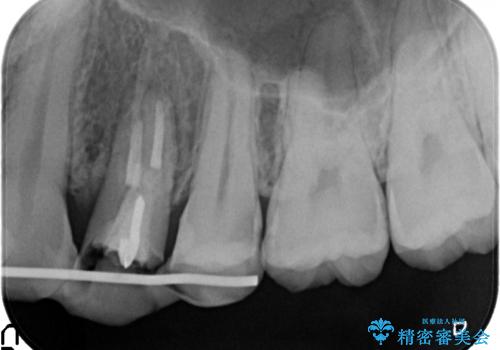

左上4の補綴物を除去したところ縁下歯質だったため、歯牙の挺出を提案し行いました。

挺出終了後は歯肉切除および骨外科により歯周組織を整え、オールセラミッククラウンによる補綴を行いました。